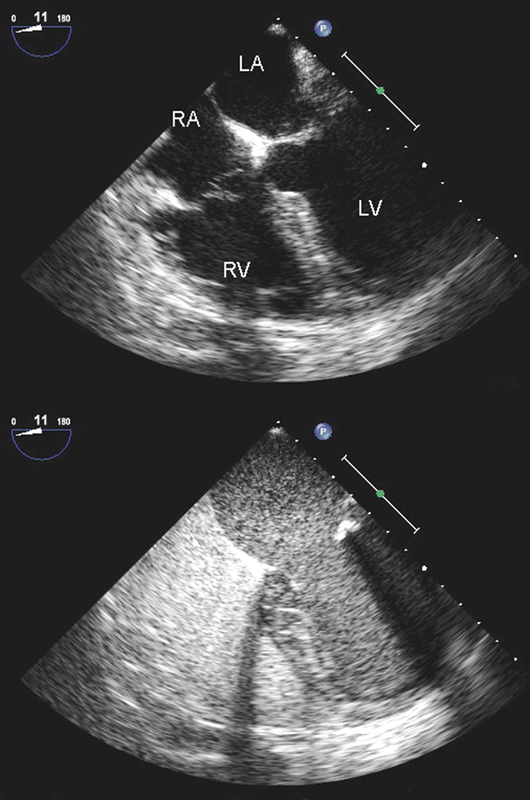

فحوصات تشخيصية لبعض امراض القلب والشرايين التاجية